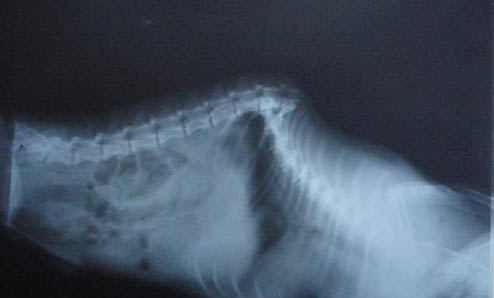

犬猫不明原因发热主要从三个阶段分析,

1、全面病史调查和体格检查,通过问诊,触诊等了解记录犬猫基本情况。

2、通过非侵入式或侵入式检查,包括血常规,生化,尿液检查等去检查鉴别诊断,排出相关病因。

3、前面阶段未诊断出结果,可尝试进行治疗性实验。